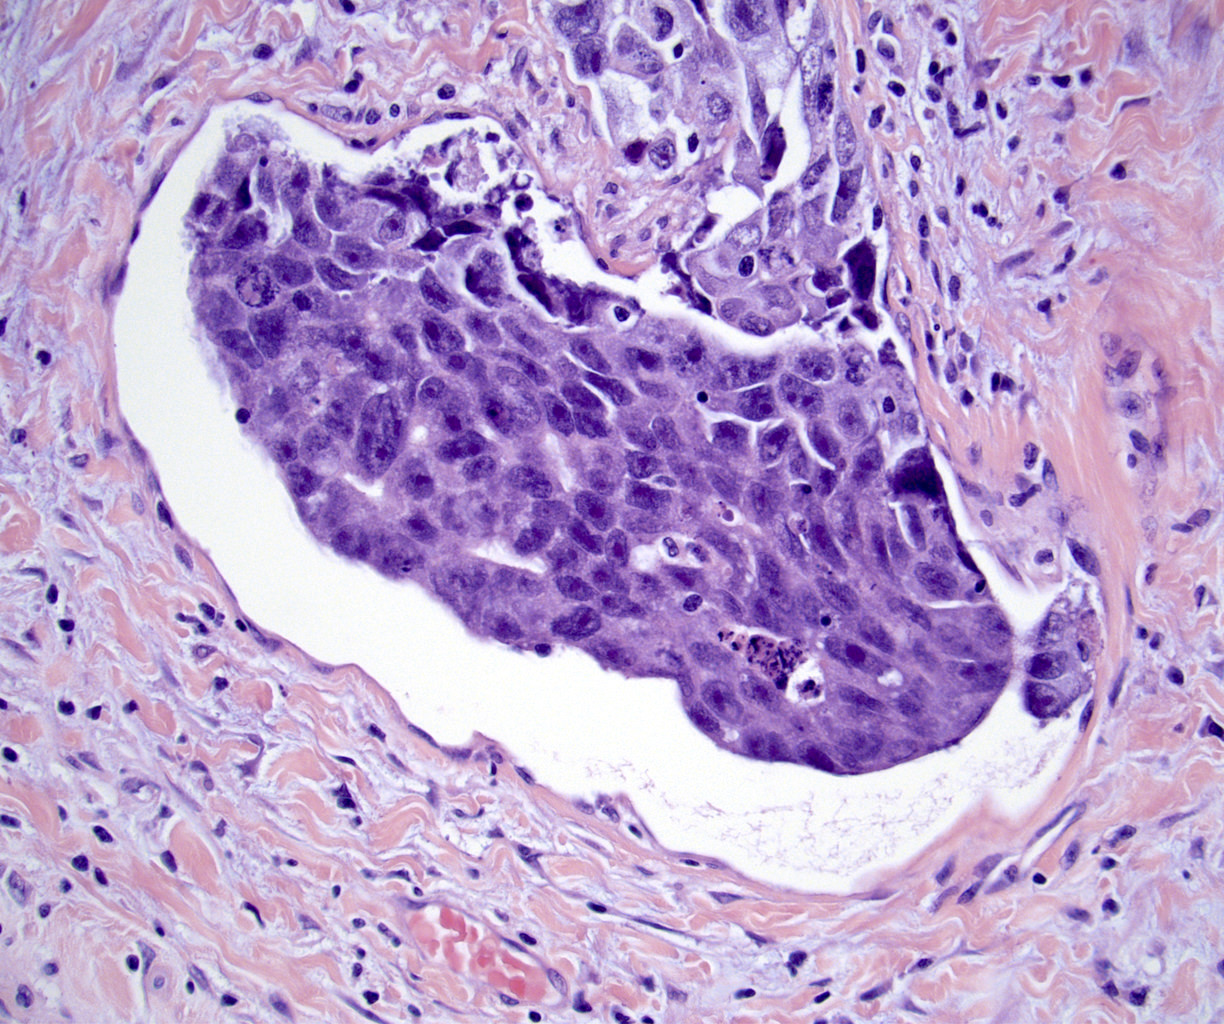

Microscopic (histologic) images

Board review style question #1

In a postpubertal testicular germ cell tumor, lymphovascular (shown above), hilar fat, epididymal and tunica vaginalis invasion are all a part of which pT category?

- pT2

Board review style answer #1

D. pT2. Lymphovascular, hilar fat, epididymal and tunica vaginalis invasion are all a part of the pT2 category for testicular germ cell tumors. Lymphovascular invasion by embryonal carcinoma is shown in the image.

Comment Here Reference: